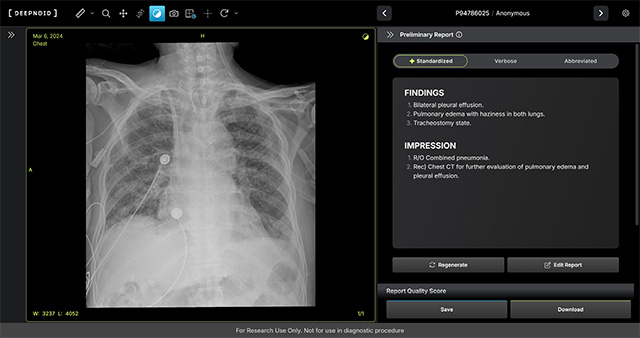

• M4CXR 판독 예시 /이미지 제공=딥노이드

▲ M4CXR 판독 예시 /이미지 제공=딥노이드

회사에 따르면 M4CXR은 흉부 X-ray 영상에서 41종의 병변을 분석해 수초 내 판독 소견서 초안을 자동 작성할 수 있는 것이 특징이다. 약 1,000만 건 이상의 판독 데이터를 기반으로 학습된 생성형 AI를 적용해, 영상의학과 전문의의 판독을 보조하고 응급 상황에서 신속한 예비 판독 결과를 의료진에게 제공할 수 있다는 설명이다.